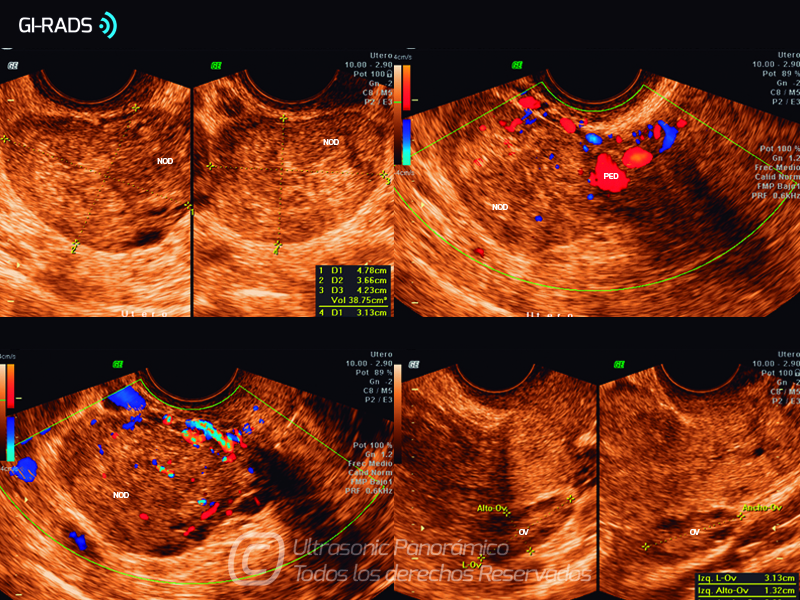

Patologías Benignas – Mioma Pediculado